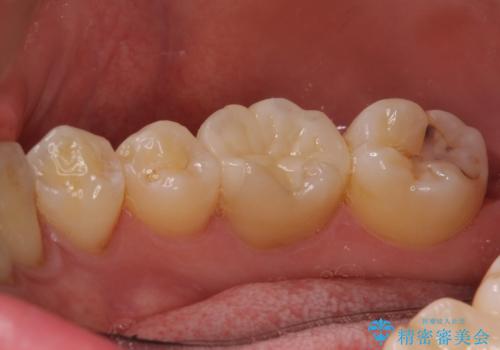

そのため左上4番目の歯は根管治療を行い、歯茎の膿の出口の消失を確認後、オールセラミッククラウンによる補綴を行いました。

今回用いたオールセラミッククラウンはジルコニアフレームという白い素材の上にセラミックを盛っているため、審美性が非常に高いのが特徴です。

また、ジルコニアは人工ダイヤモンドの材料にも使われているほど高い強度を持っており、そのためオールセラミッククラウンは審美性だけでなく、奥歯やブリッジの補綴も可能とするクラウンです。